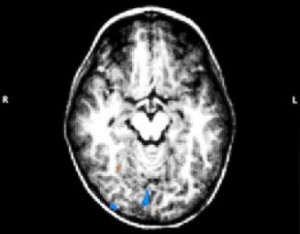

Образни. Показани са при абнормни размери на главата, гърчове, фокален неврологичен дефицит. Най-информативна е МРТ, но КТ има по-голяма точност за калцификати, а някои метаболитни заболявания изискват магнитно-резонансна спектроскопия. Положителни резултати се откриват при около 20%.